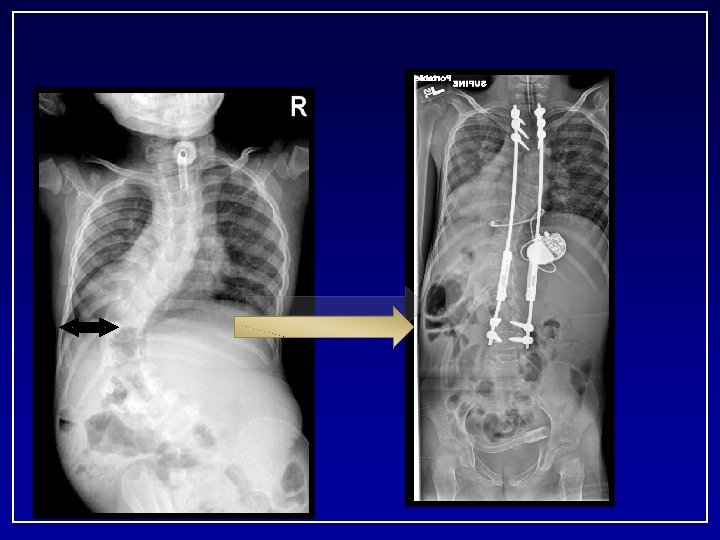

- At the age of 4 y. o - Upper foundation T 5 -6 (Transverse process hooks) - Lower foundation L 1 -2

Biomechanical Comparison of Different Anchors and Foundations in the Dual Growing Rod Technique* Mahar A, Bagheri R, Oka R, Kostial P, Akbarnia BA 1 San Diego Center for Spinal Disorders, La Jolla, CA 2 Orthopaedic Biomechanics Research Center, Children’s Hospital, San Diego, CA 3 Department of Orthopaedics, University of California, San Diego. Spine Journal 2008

C. C. • 9+7 yrs Boy • Multiple congenital anomalies – Tracheomalacia(s/p tracheostomy, g-tube) – Normal neuro/development milestones – History of multiple pneumonia’s • Initially presented 3/01 at age of 2. 5 yrs • 20° curve progressed to 68° • Failed non operative treatment x one year

57 months after initial surgery 38 CC Age 7+3 Cobb: Pre 86° FU 38° T 1 -S 1: Pre 211 mm Post 247 mm FU 301 mm Total 9. 0 cm Length. 9

April 2008 • • Exploration of fusion Removal Implants New Implants Revision T 3 -T 5

9. 3. 2008 - 7 years post op • T 9 -L 3 40 deg • T 2 -T 9 45 deg Kyphosis • T 3 -T 12 48 deg • T 12 -S 1 42 deg Growth T 1 -S 1 Pre: 211 cm Post: 247 cm FU: 338 cm Total lengh: 12. 7 cm Expected growth: 9 cm # lengthening: 13

The bumpy road to success • • 9 years and 7 months 20 surgeries in last 7 years 13 lengthenings 6 revision surgeries (instrumentation) 5 Irrigation and Debridements 3 wound dehiscences requiring OR intervention 2 Deep infections requiring PICC line and 6 weeks of abx